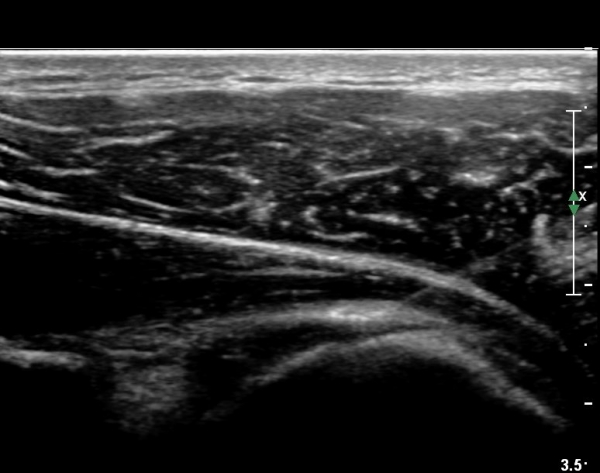

ÆÈÀ» ¿ÜȸÀüÇϸ鼭 °üÂûÇÏ´Ï °ß°©ÇÏ±Ù°Ç ÆÄ¿­ÀÌ ¶Ñ·ÈÇÔ(»çÁø 2, 3).

°ß°©ÇÏ±Ù°Ç »óºÎ Á¾´Ü¸é°Ë»ç¿¡¼­ °ß°©ÇϱٰǠ ÆÄ¿­ÀÌ ¶Ñ·ÈÇÔ(»çÁø 4, 5).